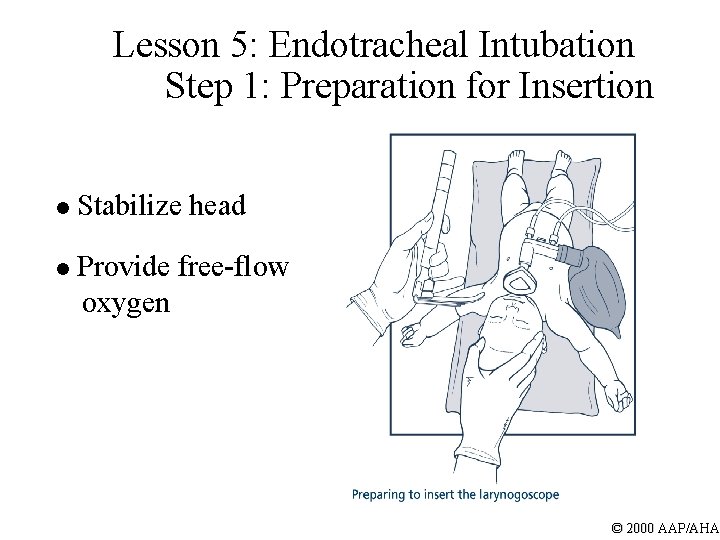

Lesson 5: Endotracheal Intubation Step 1: Preparation for Insertion l Stabilize head l Provide free-flow oxygen © 2000 AAP/AHA